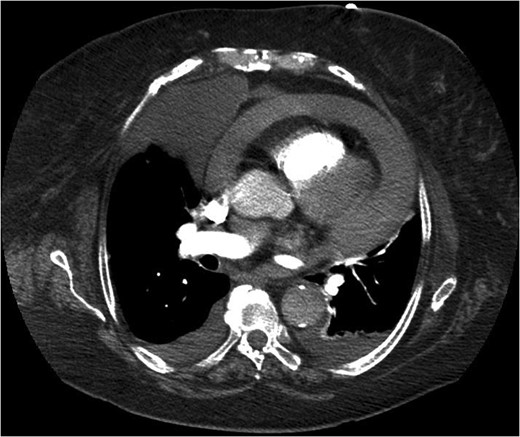

An 83-year-old woman presented to accident and emergency with sudden symptoms of abdominal pain and vomiting. She had presented a month earlier with similar symptoms and dysphagia, which had been ongoing for 2 weeks. Clinical examination had shown reduced air entry in the right lung and a normal abdomen. Chest X-ray showed consolidation in the lower right zone but with no symptoms or signs of a lower respiratory tract infection. She was taken under the care of the medical team and went on to have a computed tomography (CT) scan (Fig. 1) of her chest, which revealed a Bochdalek's hernia. Her symptoms settled, and she was discharged without a surgical review.